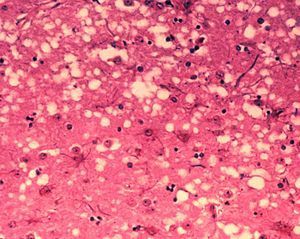

有网友说只要煮熟了就行了"是不行的,就单纯从库鲁病的角度来说煮熟是没有用的,因为引起发病的是一种叫普里昂的蛋白质,他们能病毒性的传染,但最终的它不是病毒也不是细菌,也就意味着它不是生物,不是生物也就是说它无法被杀死。

普里昂蛋白

火烤可能还稍微好一点,但煮肯定是煮不死的,用一般的药物由是毒不成者去除不掉的。所以库鲁病到现在都是绝,不法治疗的。这种普里昂蛋白质,主要存在于人脑之中,以吃脑子是最危胎的,吃身上的肉还能好一点,但也不能确保,这肉里面就没有这种蛋白,所以整体来说吃人肉定非常危险的哦。